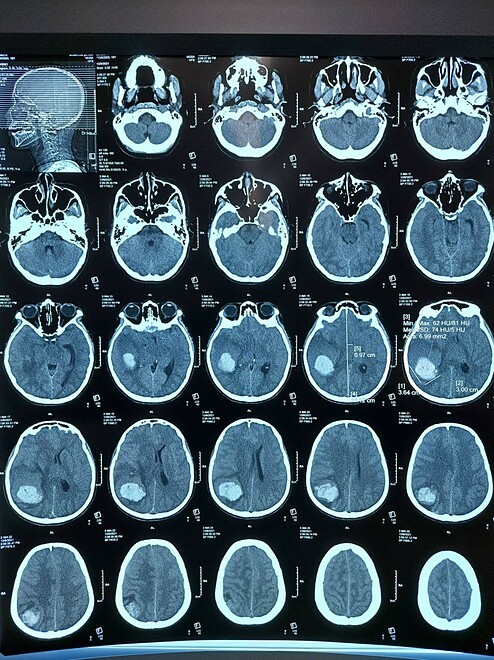

Cô gái 18 tuổi ở Hải Phòng, cảm thấy đau đầu, buồn nôn, vào giường nằm nghỉ, thiếp đi, nhanh chóng rơi vào trạng thái lơ mơ

Nguồn: https://vnexpress.net/co-gai-18-tuoi-dot-quy-4401427.html